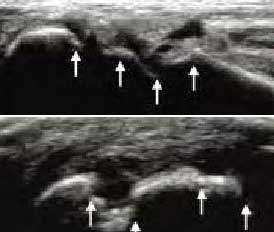

类风湿性关节炎以滑膜炎为基本病理改变,超声可观测到关节暗区的范围及厚度,判断有无滑膜增厚、显示不同程度的滑膜均匀或不均匀增厚,分辨滑膜呈绒毛状、团状或结节状结构向关节腔突起的形态。通过对滑膜厚度、水肿、炎性细胞浸润状况的分级、定量评估RA关节内滑膜的炎性程度。

Ⅰ级滑膜增生

轻度滑膜增生,不超过骨面 点连线

Ⅱ级滑膜增生

滑膜增生超过骨面 点连线,呈绒毛状,但不越过骨干

Ⅲ级滑膜增生

滑膜增生超过骨面 点连线,呈团块状延伸超过一侧骨干